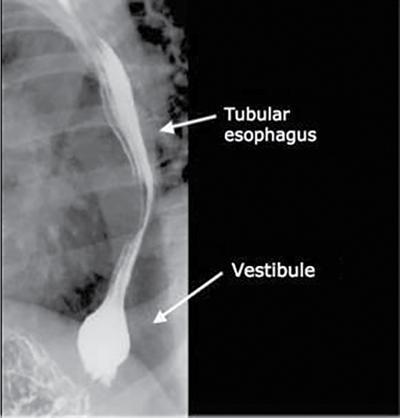

• Lower oesophageal sphincter (Fig. 7.3.5).

• It is noted on barium swallow study.

• Bulbous distension of distal 2–4 cm of lower oesophagus is called vestibule and corresponds to the manometrically defined high-pressure zone that constitutes the lower oesophageal sphincter.

• It is best demonstrated by breath-holding in inspiration or Valsalva manoeuvre.

Fig. 7.3.5 Lower oesophageal sphincter on barium swallow.